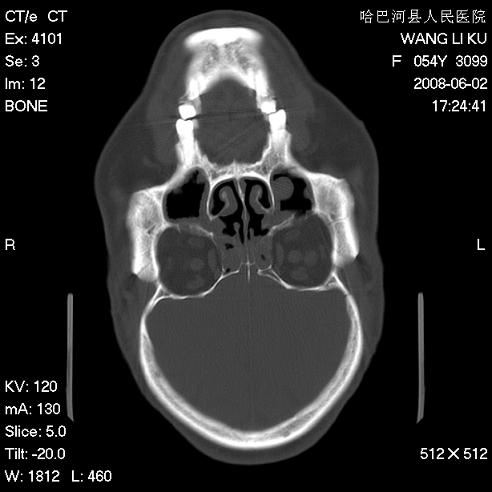

标题: CT13803:反复性鼻塞、流涕一年余 [打印本页]

标题: CT13803:反复性鼻塞、流涕一年余

副鼻窦炎,右上额窦积脓。左眼肌锥内见致密影,视神經受压

1.全组副鼻窦炎2.双侧上颌窦积液

全组副鼻窦炎 肌锥内高密度灶。建议进一步检察检查

1、全组副鼻窦炎。

2、左眼眶肌锥内病变,小血管瘤?建议增强。

1)全副鼻窦炎(左侧上颌窦黏膜下囊肿或息肉)。2)左眼眶肌锥内不规则小结节状软组织密度影;考虑为小血管瘤可能。建议行ct增强扫描检查。

全组副鼻窦炎,左侧肌锥内不规则形软组织肿块影,与眼外肌密度相当,左侧视神经受压,肿块与视神经及眼外肌分界清晰,眼外肌无增粗,眶壁无破坏,球后脂肪间隙不模糊,考虑良性改变,小血管瘤或神经源性肿瘤可能,建议增强扫描。

谢谢,增强扫描做了,眶内病灶与海绵窦同步明显强化,血管瘤